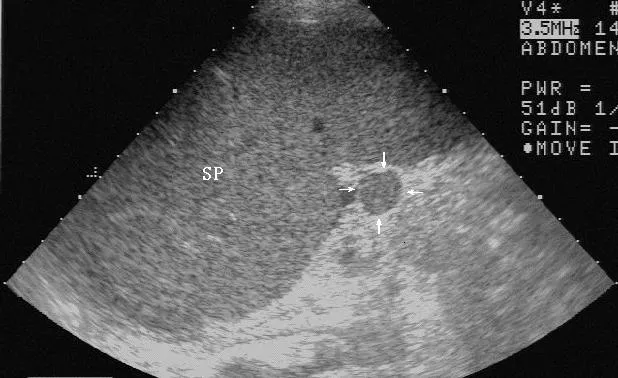

灰阶超声,副脾,显示脾门处一圆形回声与脾回声类似的副脾(箭头所示)

SP:脾脏